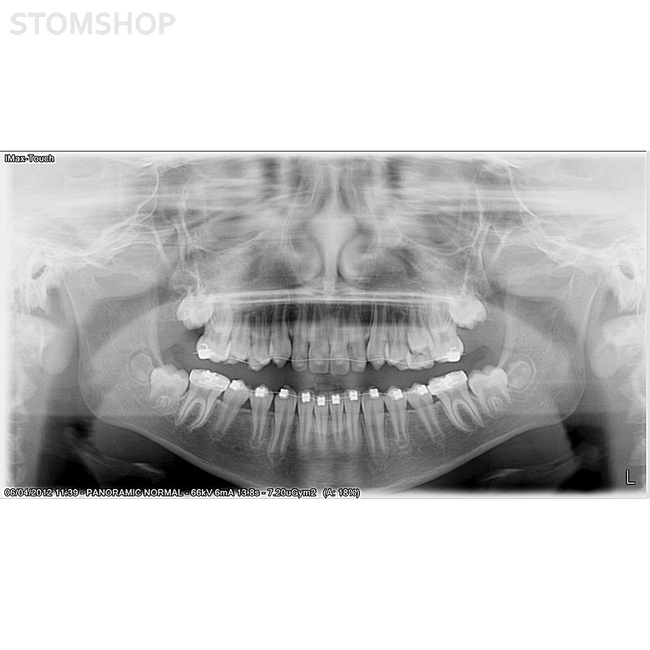

Ортопантомограф I-Max Touch Pano предназначен для получения панорамных снимков челюстей у взрослых и детей. Вывод изображения осуществляется на монитор, экран пульта и на флеш-карту. Значительное уменьшение дозы рентгеновского излучения. Полностью компьютеризированное управление. Без цефалостата.